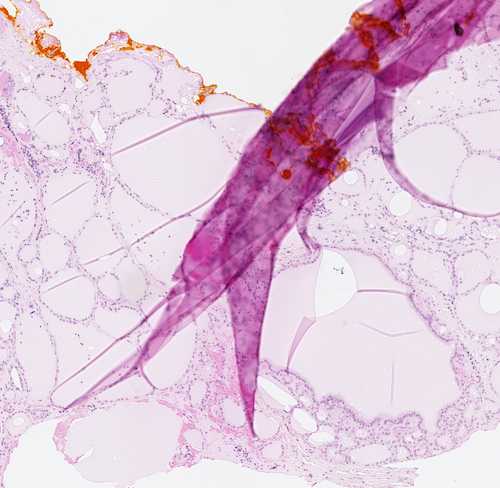

Regardless whether we use digitization or microscopy, the presence of artifacts such as folded tissue might negatively affect the diagnosis [4]. When digital technology is used other artifacts like blur may also reduce the quality of computerized algorithms [10]. Tissue fold can occur in the sectioning part of tissue processing when a thin tissue slice is folded [11]. Figure 1 shows three samples of folded tissue.

[5pt] \stackunder[5pt]

\stackunder[5pt] \stackunder[5pt]

\stackunder[5pt]